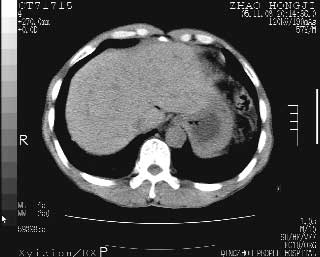

临床资料:男性,57岁,上腹部疼痛并5天,突然加重并延及全腹伴恶心5小时入院。胰淀粉酶化验在正常范围。检查:腹肌紧张,全腹压痛、反跳痛,尤以右上腹部为著。肠鸣音减低。血常规:wbc14.6x10/9, n:11.3x10/9 ,血压:135/90mmhg. 胸部透视:腹部肠腔轻度张气,未见其它异常改变。

肝右前缘少量积气,其他未见明显异常.考虑上消化道穿孔.

小网膜囊积气液,胃壁僵硬。考虑胃穿孔。

小膜网膜积液,肝缘气腹征,上消化道穿孔。

肝缘见少许气体,胰尾部见少许气体包饶(蓝色圈),12指肠上部或球部邻近胆囊周边也可见少许气体影(黄色圈),并忖托出胆囊壁,12指肠远段肠道内未见明显气体(白色箭)。

肝脏前缘见少量积气、胰尾部见少许气体包饶,肾前筋膜未见增厚,临床淀粉酶不高,意见:上消化道穿孔。

关于本病例的术后诊断:

入院3小时后行剖腹探查术,见腹腔内大量脓性混浊液约1000ml,十二指肠球部溃疡穿孔,溃疡面约2.5x2cm,穿孔直径约0.6cm。胃内容物外益,周围组织炎性水肿明显。行十二指肠穿孔修补术。术后诊断:

1、十二指肠溃疡穿孔

2、弥漫性腹膜炎

对于少量的腹腔游离气体,ct检查较普通透视有绝对的优势,它不仅可以看到肝脏前上缘的气体,而且还能够看到小网膜区的游离气体。从而可以肯定诊断。各位分析战友的很好,感谢大家的参入!